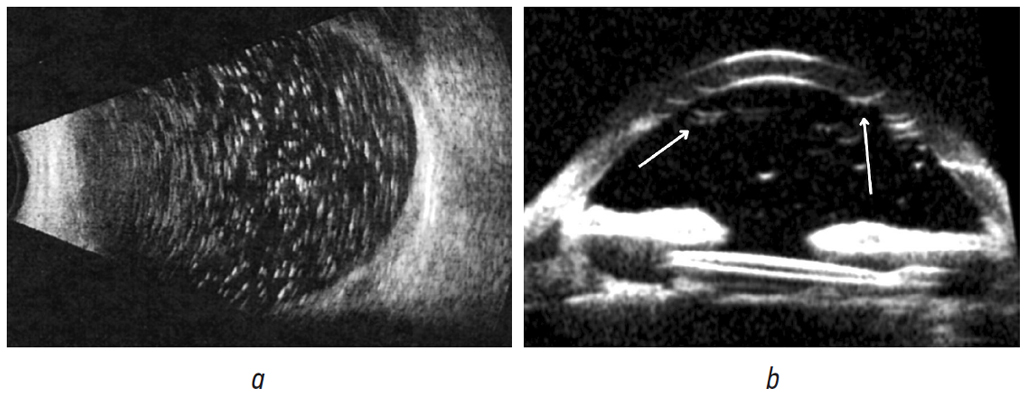

B-scan and ultrasound biomicroscopy revealed settlement of emulsified silicone oil droplets on the eye structures (Fig. 3).

Fig. 3. B-scan: Multiple drops of emulsified silicone oil in the vitreal cavity (a). Ultrasound biomicroscopy: deposition of silicone oil droplets on the corneal endothelium, iris surface, capsule and zonules; silicone bubbles are indicated by arrows (b)

Рис. 3. В-сканирование: множественные капли эмульгированного силиконового масла в витреальной полости (a). Ультразвуковая биомикроскопия: отложение капель силиконового масла на эндотелии роговицы, поверхности радужки, капсуле и связках хрусталика; стрелками указаны пузырьки силикона (b)